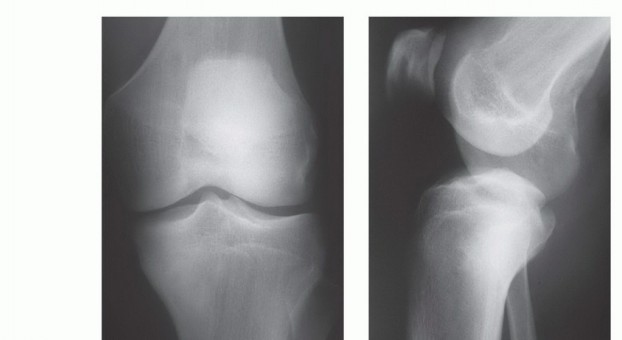

- الأشعة السينية (X-rays): هي الخطوة الأولى، وتُظهر التغيرات في بنية العظم، مثل التدمير العظمي، أو تكوين العظم الجديد، أو رد فعل السمحاق.

- التصوير بالرنين المغناطيسي (MRI): يُعتبر الأداة الأكثر أهمية لتحديد مدى انتشار الورم داخل العظم، وفي الأنسجة الرخوة المحيطة، وعلاقته بالأوعية الدموية والأعصاب. يُساعد في تحديد هوامش الاستئصال الجراحي.

تتنوع أورام قصبة الساق القريبة بين الحميدة والخبيثة، ويُعد التشخيص الدقيق لنوع الورم ومدى انتشاره الخطوة الأولى والأكثر أهمية في وضع خطة علاج فعالة.